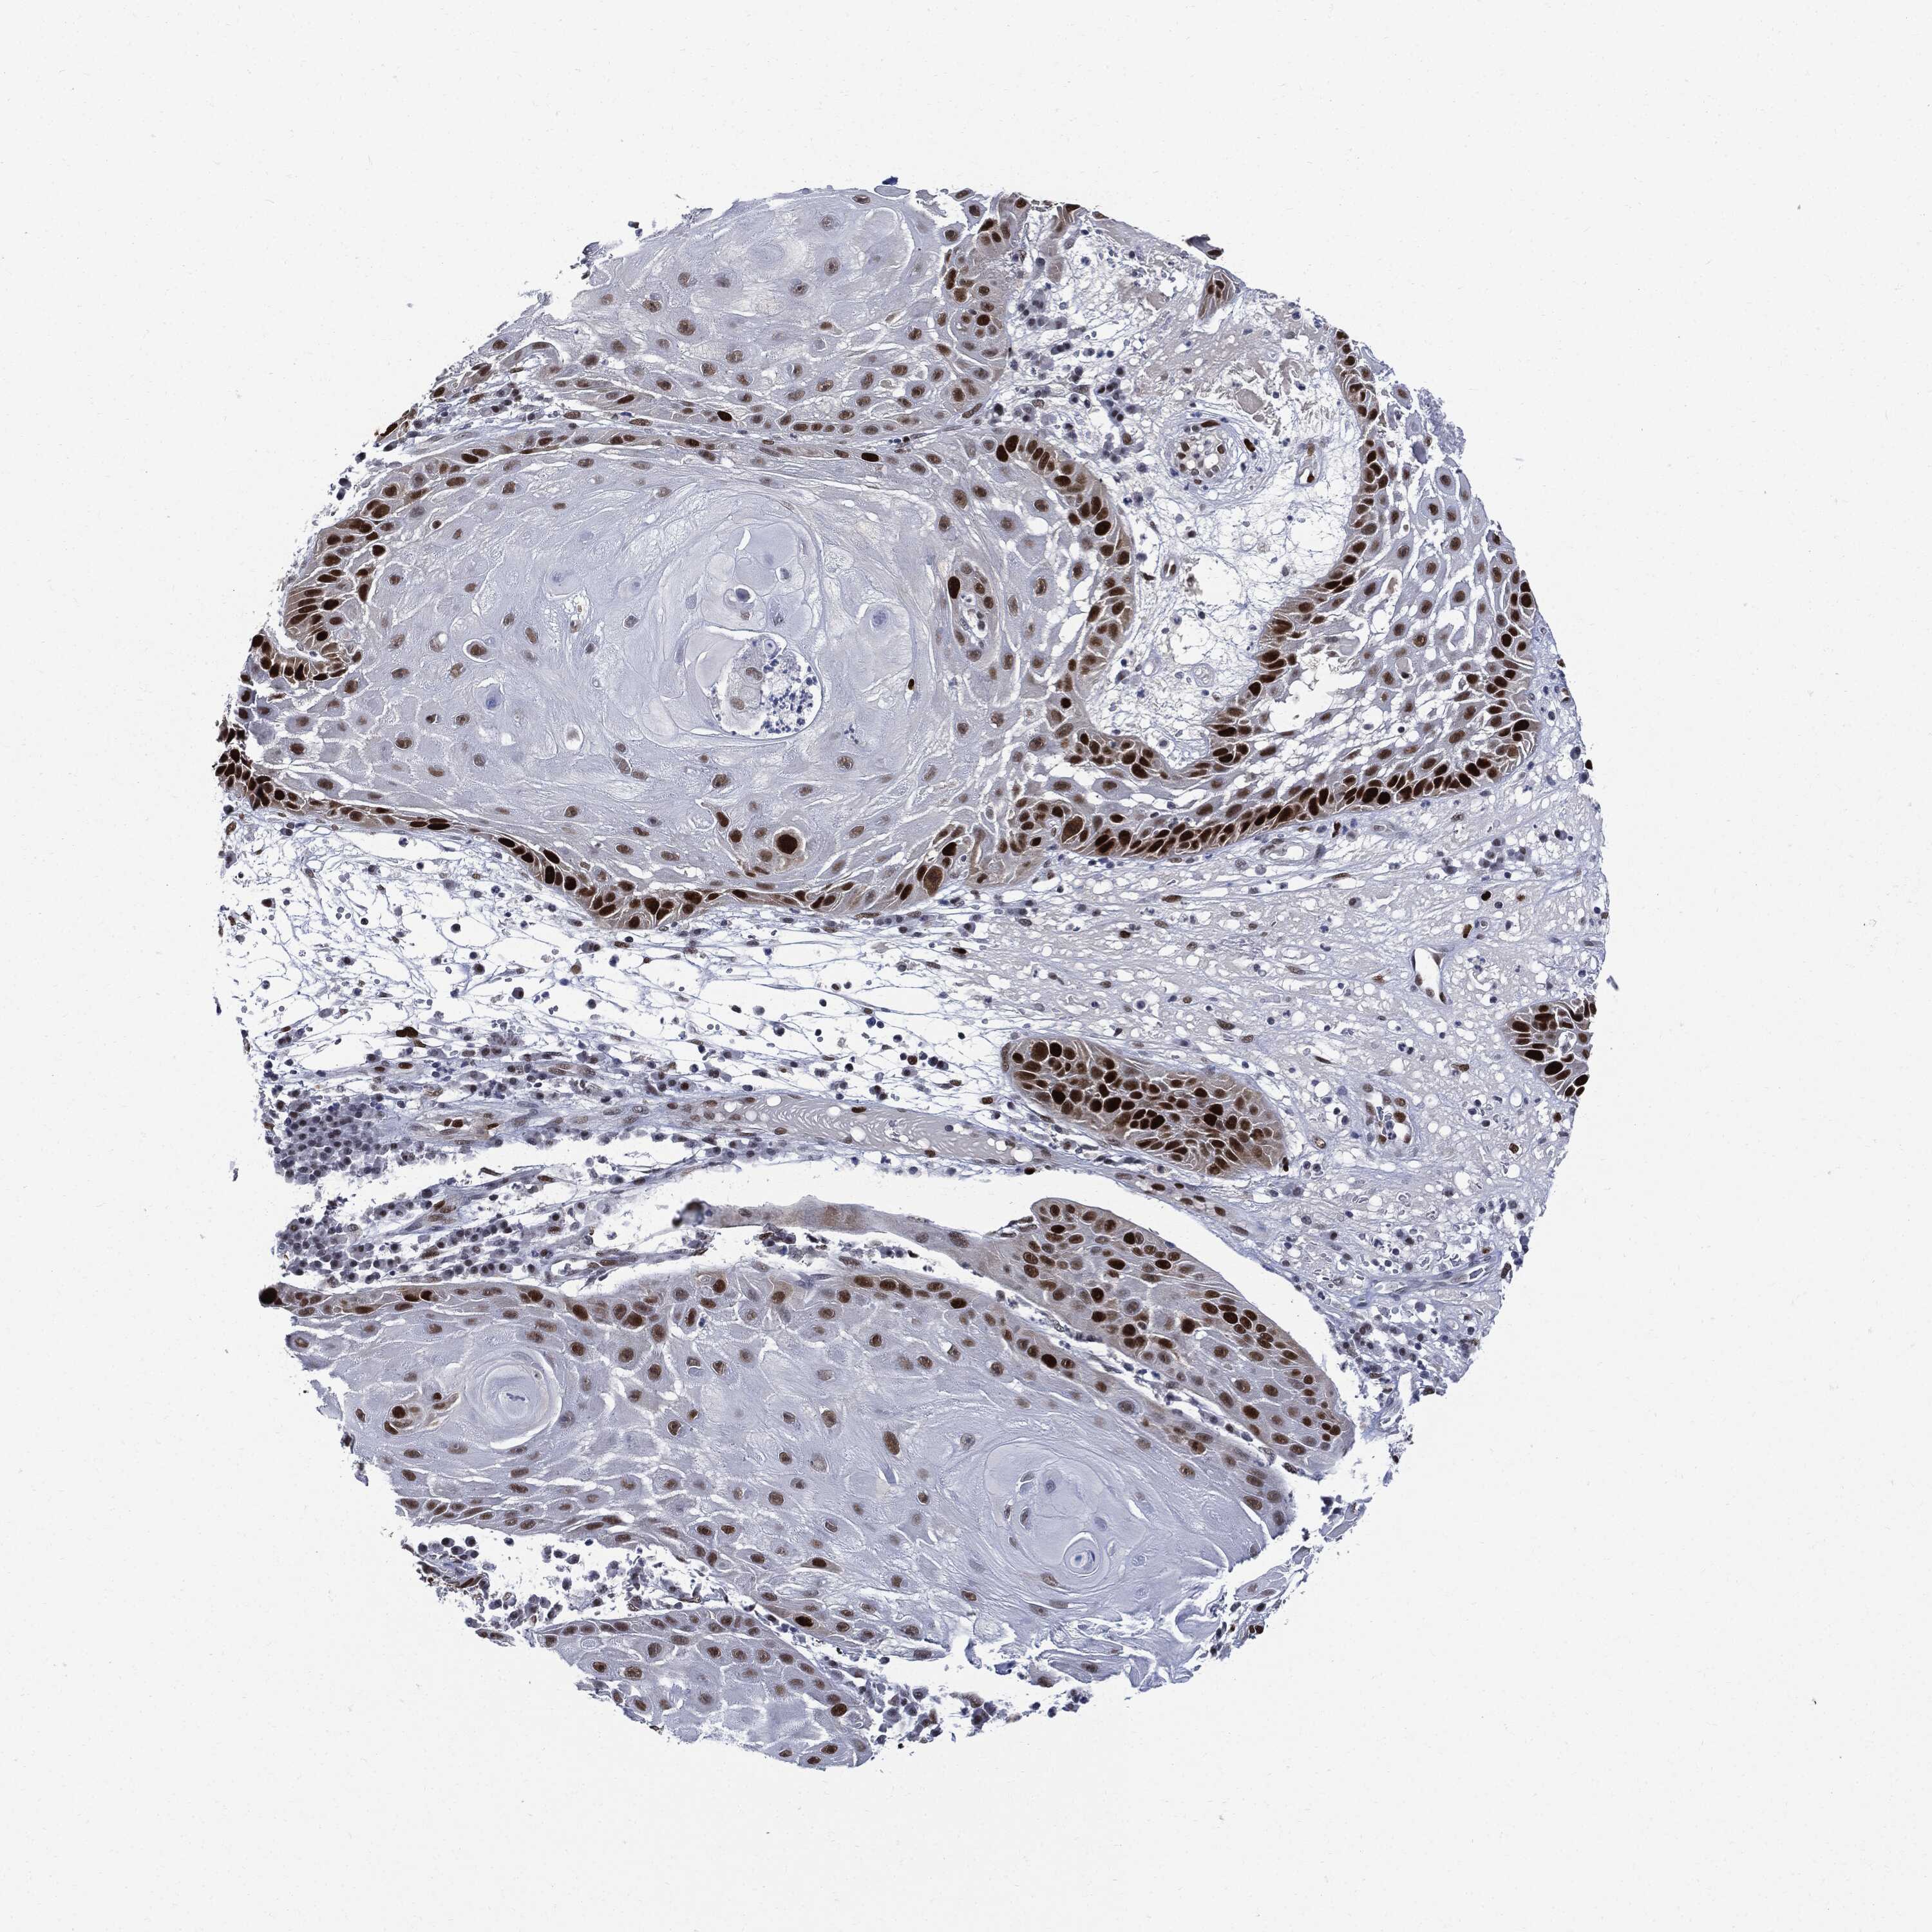

Basal cell and squamous cell cancer

SKIN CANCER - Protein expressioni

A mouse-over function shows sample information and annotation data. Click on an image to view it in a full screen mode. Samples can be filtered based on level of antibody staining by selecting one or several of the following categories: high, medium, low and not detected. The assay and annotation is described here.

Each image is clickable and will lead to virtual microscopy that enables deeper exploration of all samples and also displays staining intensity scores, fraction scores and subcellular localization as well as patient and tissue information for each sample.

Basal cell carcinoma

Squamous cell carcinoma, NOS

Squamous cell carcinoma, metastatic, NOS